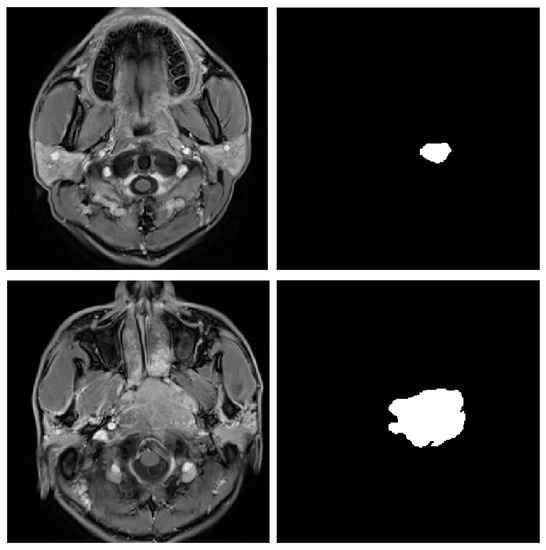

DCNet: Densely Connected Deep Convolutional Encoder–Decoder Network for Nasopharyngeal Carcinoma Segmentation

4.1. Data Acquisitions

4.3. Experimental Results